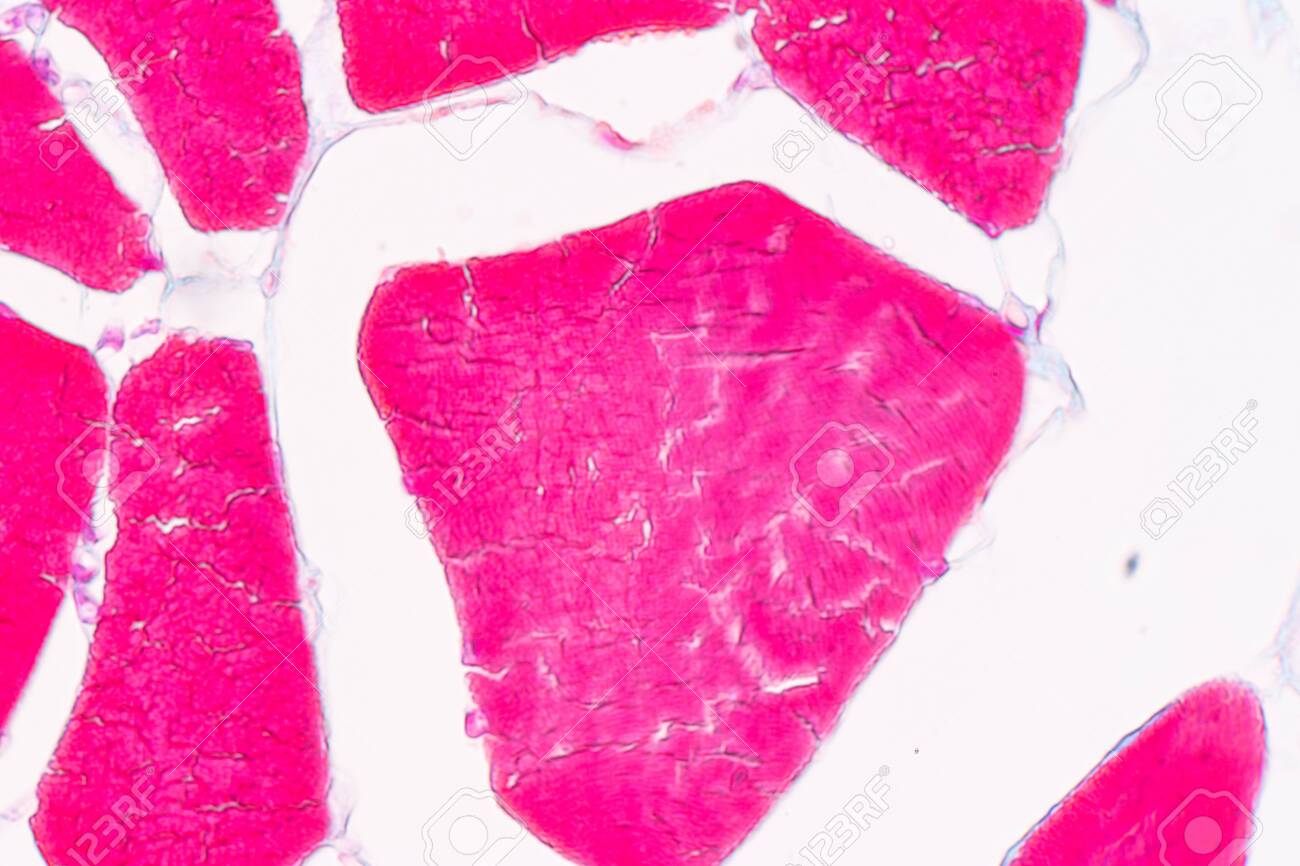

Muscular system anatomy muscle types. Under the light microscope muscle cells appear striated with many nuclei squeezed along the membranes.

Education Anatomy And Histological Sample Striated Muscle Tissue